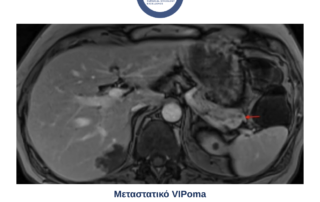

Πρόληψη και αντιμετώπιση του Καρκίνου του Παγκρέατος Ο καρκίνος του παγκρέατος αποτελεί μέχρι και σήμερα ένα από τα επιθετικότερα και δύσκολα αντιμετωπίσιμα[...]